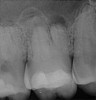

Figure 1. THROUGH Figure 3. Root filled with bioceramic sealer cut at different distances from the apex (left to right: 0.5, 1.5, and 3.0 mm). One gutta-percha point is used as a plugger to move the sealer using hydraulic pressure. Note the irregularities are very well filled.

Figure 1

Figure 2